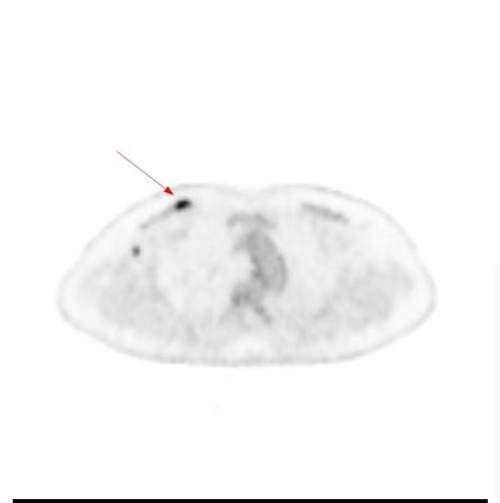

PETCT显示右侧乳腺内糖代谢明显增高的结节和腰椎的转移癌

问题来了,彭女士腰椎转移癌原发灶在哪里?是甲状腺癌吗?因关系后续治疗方案,在医生的建议下,彭女士到捷克论坛 PET影像中心进行PET/CT扫描。检查结果让人大吃一惊,彭女士的右侧乳腺有一个糖代谢明显增高的结节,大小为10mm,高度提示右侧乳腺癌。这下解开了腰椎转移癌的谜底,乳腺癌除腰椎骨转移外,同时发现右侧腋窝淋巴结和骨盆多骨的转移。目前,彭女士已经转入乳甲外科接受手术及进一步治疗。